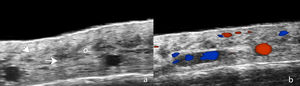

For its part, UHFUS in FFA has reported findings such as perifollicular hypoechogenicity in the mid-dermis, distal ambiguity of hair follicles, and undulating hyperechoic bands in the subcutaneous cellular tissue (Fig. 2). The first 2 were also observed in LPP and corresponded in histopathology to perifollicular fibrosis and inflammation in the promontory and to inflamed or destroyed follicles in the isthmus or infundibulum, respectively. In turn, the hyperechoic bands in the subcutaneous tissue corresponded to fibrous septa distributed linearly in the hypodermis.8 Another ultrasound study in 99 women with FFA and 40 controls showed greater vascular diameter and greater flow in the hairline area vs the alopecic band area and the control group, which can be explained by both active inflammation in the frontal line and fibrosis in the alopecic band. In addition, the diameter of the vessels was significantly greater in the healthy scalp area of patients with FFA vs the control group, which could be explained by subclinical inflammation and could be a predictor of future progression.14

Ultrasound of frontal fibrosing alopecia. (A) Loss of hair follicles (*) and subcutaneous adipose tissue. Loss of definition of the dermohypodermal border (oblique arrow), increased subcutaneous echogenicity (o), and prominent subcutaneous lamellar structures (horizontal arrow). (B) Color Doppler of the same region demonstrates increased dermal vascularization.